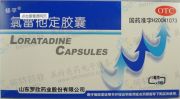

| 2021年7月26日 (一) 20:01 | 氯雷他定.jpg (文件) |  |

51 KB | 77921020 | Uploaded with SimpleBatchUpload | 3 |